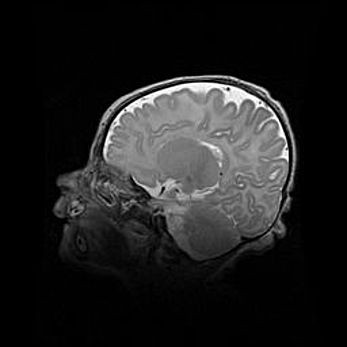

Сообщающаяся гидроцефалия. Кистозная энцефаломаляция головного мозга.

Возраст: 3 месяца 4 дня

Вес: 3100 г

Пол: женский

Окружность головы: 34 см

Срок гестации: 31 неделя

Кистозная энцефаломаляция головного мозга - одна из форм поражения головного мозга в детском возрасте. Характеризуется возникновением множественных и распространённых кист в коре, белом веществе и подкорковых образованиях головного мозга у плодов, новорождённых и детей раннего возраста. Развитие кистозной энцефаломаляции связано с внутриутробной асфиксией и гипотонией, родовой травмой, тромбозом синусов, пороками развития сосудов, инфекциями, сепсисом и другими причинами. Наиболее значимые инфекционные агенты: вирусы простого герпеса, цитомегалии, краснухи, токсоплазмы, энтеробактерии, золотистый стафилококк и другие.